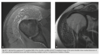

61yr old woman with shoulder pain

A

AP Radiograph of left shoulder in external and internal rotation (1 & 2) - globular foci of calcification in expected location of supraspinatus (White arrow) and infraspinatus (black arrow) and pectorals major

DIAGNOSIS: Hydroxyapatite deposition disease

(HADD)

HADD consists of crystal deposition in

and around joints, without a known cause.

AKA calcific tendonitis

On radiographs, the calcium deposits appear cloud-

like and amorphous and can involve the tendon,

ligament, bursa, or joint capsule. Intraarticular crys-

tal deposition can destroy the joint space, resulting

in a condition referred to as “Milwaukee shoulder.”

On CT,

­ accompanying erosion of the underlying bone can be

seen. CT appearance has been described as commonly

having a flame-shaped or comet-tail configuration of

the calcifications

If not in shoulder/region not common for HADD ?Malignancy